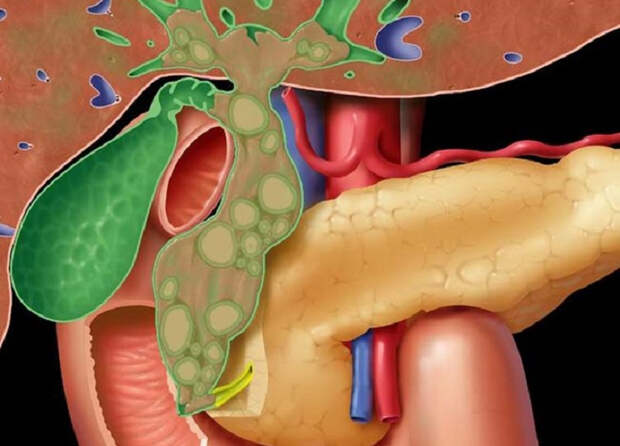

Анатомия и особенности Гартманова кармана желчного пузыря